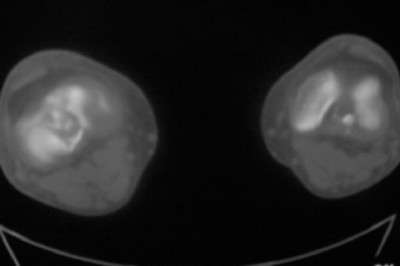

标题: CT8024:会诊!!!男 60 岁 双漆关节疼痛半年,进行性加重 [打印本页]

患者男 60 岁 双漆关节疼痛半年,进行性加重.

右股骨内髁关节面下多个不规则小囊变,边缘有明显硬化边,.......考虑: 1.关节面下骨囊变.  2.类风湿关节炎?   3.血友病?

右侧髁间隆突变尖,软骨下假囊肿形成,结合病人年龄较大,首先考虑退行性骨关节病。关节周围软组织未见明显异常,病人单单一双膝关节出现症状,不太支持类风湿性关节炎,可结合化验室检查。